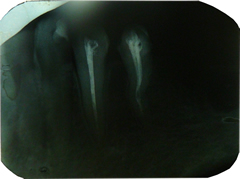

Obturatie de canal canal curbat

Tratamentele endodontice se fac cu radiografie si cu aparat automat endodontie, folosind in mare majoritate materiale biocompatibile, datorita raspunsului apical mai bun. Unii dinti au mai multe canale, pretul variind in functie de aceasta. De regula se calculeaza impreuna cu obturatia finala de la: